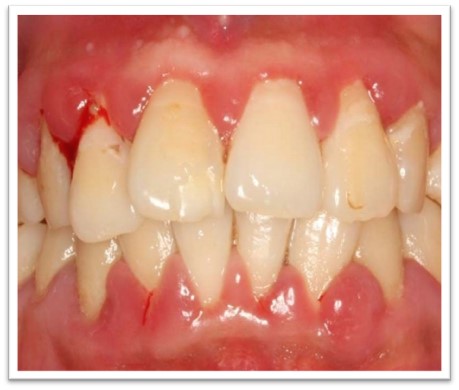

炎症水肿型(图10.1-1):龈缘红肿、光亮、松软,易出血。

图10.1-1 慢性龈炎(炎症水肿型)